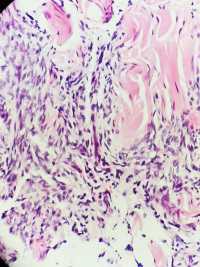

性别年龄32临床诊断

一般病史腹部肿物2年,术中见肿物紧邻皮下,与皮肤无黏连,肿物表面有粘液感,光滑

标本名称腹部肿物

大体所见灰粉结节一枚4*3.5*3cm,无包膜,切面灰粉实性质中,较细腻光滑

隆突,建议IHC标记排除腹壁纤维瘤病。

本例要鉴别的病种很多;建议:1.VIM;MUC4;SMA;SMA排除低度恶性纤维粘液样肉瘤;2,CD34排除“隆突”3.β-CATENINI,排除纤维瘤病;4.S-100,排除神经和脂肪来源;5。还需排除结节性筋膜炎的可能。

首先考虑隆突,建议做免疫组化协助与其他梭形细胞肿瘤相鉴别。

会诊结果:隆突。感谢各位老师!